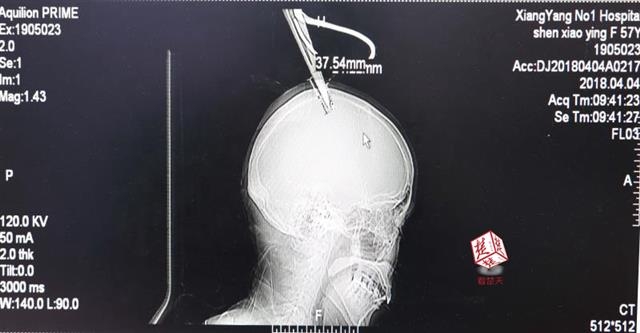

醫(yī)生檢查發(fā)現(xiàn),剪刀刀尖斜嵌在沈某顱骨里,離腦髓只有兩三毫米。所幸是斜著插進(jìn)去,如果是垂直刺入,很有可能造成癱瘓。

4月4日清晨,襄陽市樊城區(qū)太平店鎮(zhèn)57歲的農(nóng)村婦女沈某,在采摘香椿嫩芽時(shí),綁在竹桿上的剪刀因竹子腐朽不慎折斷,剪刀斜插入頭顱。經(jīng)過及時(shí)搶救,目前脫離生命危險(xiǎn)。

醫(yī)生檢查發(fā)現(xiàn),剪刀刀尖斜嵌在沈某顱骨里,離腦髓只有兩三毫米。所幸是斜著插進(jìn)去,如果是垂直刺入,很有可能造成癱瘓。最終經(jīng)過手術(shù),剪刀被取出,沈某目前仍在ICU進(jìn)一步觀察。